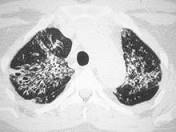

女,35岁,养鸽,咳嗽、咳痰,结合CT,考虑最可能的诊断是 ( )A.肺隐球菌病B.肺转移瘤C.支气管肺炎D.肺结核E.肺泡癌

问题 女,35岁,养鸽,咳嗽、咳痰,结合CT,考虑最可能的诊断是 ( )

选项 A.肺隐球菌病 B.肺转移瘤 C.支气管肺炎 D.肺结核 E.肺泡癌

答案 A